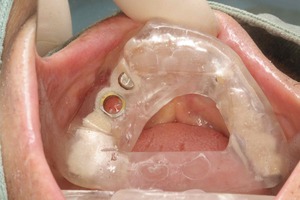

安全性に配慮して、インプラントをCTなどで予定した位置にしっかりと入れる為に

技工士さんにインプラントが、その位置にしかいかないようなカスタムメイドのマウスピースを綿密に作らせて頂きますので、神経を損傷すると行ったリスクも最大限避けることが可能になっています。